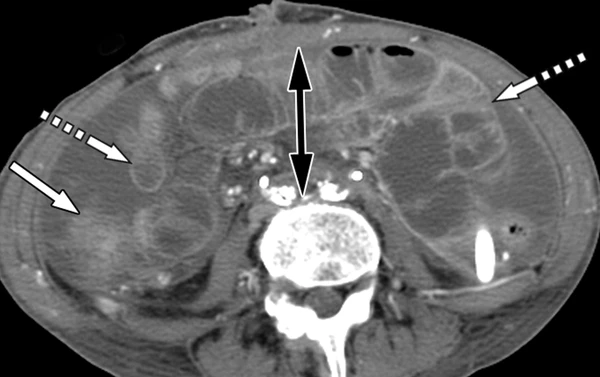

Компьютерная томография играет важную роль в выявлении косвенных признаков, позволяющих заподозрить АКС. Хотя некоторые находки, такие как уплощённая нижняя полая вена и повышенное контрастное усиление стенки кишечника («шоковая кишка»), традиционно связывают с гиповолемическим шоком, они также регулярно наблюдаются и у пациентов с АКС, даже при отсутствии выраженной гипотонии. Ключевые КТ-признаки, ассоциированные с АКС, включают[4][5]:

- сосудистые компрессионные изменения: уплощение нижней полой вены и почечных вен из-за внешнего сдавления повышенным внутрибрюшным давлением;

- патология паренхиматозных органов: наличие мозаичной перфузии печени, которая особенно характерна для пациентов с сопутствующей травмой печени. Также может наблюдаться повышение резистивного индекса печёночной артерии с резким снижением или даже реверсным диастолическим кровотоком;

- изменения со стороны желудочно-кишечного тракта: повышение контрастного усиления не только стенки тонкой кишки, но и стенки желудка. Кроме того, может наблюдаться вздутие петель тонкой кишки и выраженное растяжение желудка (гастростаз);

- изменение анатомии: высокое стояние куполов диафрагмы, являющееся прямым следствием повышенного давления в брюшной полости и смещения органов вверх.